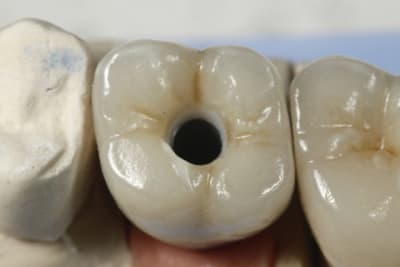

Exemple ici d'un cas ant avec

- une facette

- une ccm sur moignon metal implantaire

- une ccm sur inlay core

- une ccm a tenon.

Oui la CCM a encore de beaux jours.

Jolie prepa sur la 11.

sur la 11 l'inlay core est en métal précieux ?

L'armature de la CCM 11 l'est elle aussi ?

Pour revenir au sujet "cas esthétique" , je trouve le bord libre de 11 un peu trop translucide.

Mais j'adore l'état du parodonte!